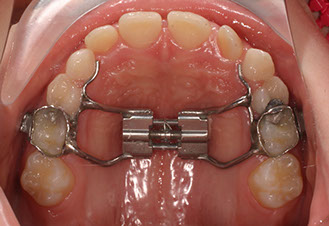

Talvolta, quando si vuole espandere l’arco palatino iposviluppato,  può essere necessario applicare un Diastasatore